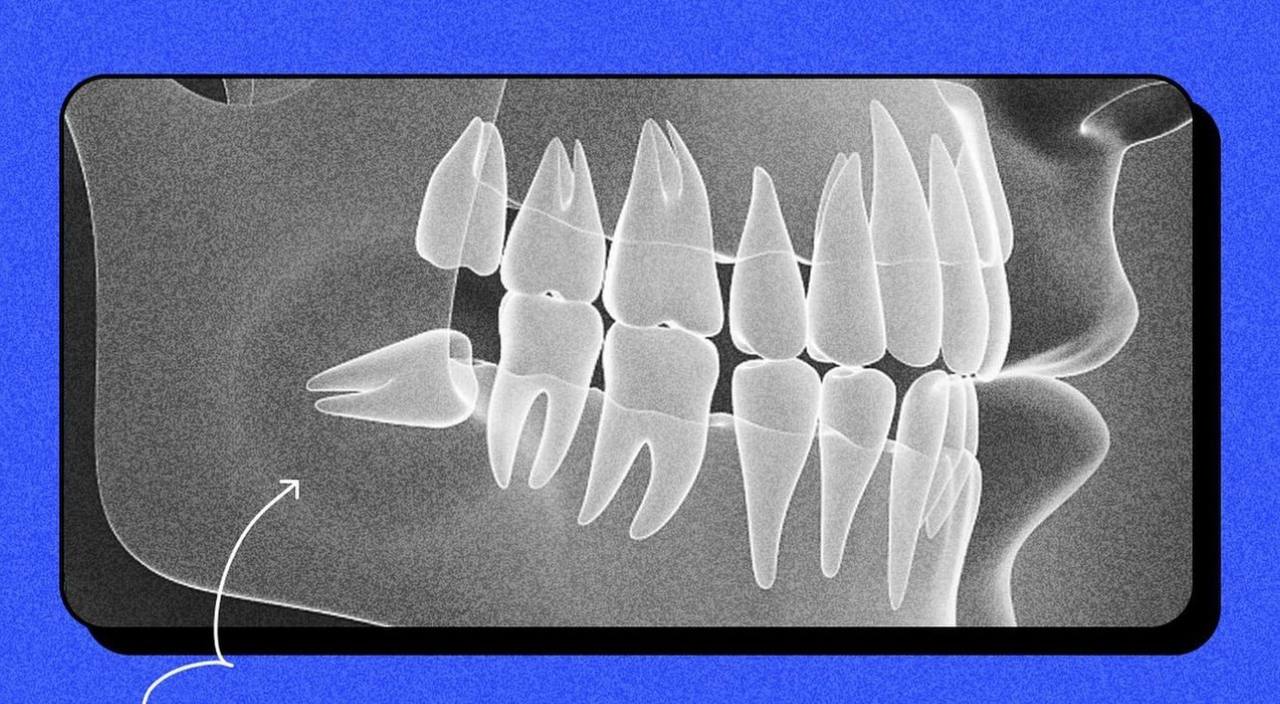

Чи завжди потрібно видаляти зуби мудрості: вся правда про "вісімки"Приклад поганого росту зуба мудрості (скриншот: instagram.com/sviy.doc)

Фахівці кажуть, якщо зуб мудрості виріс рівно, то людині пощастило. Якщо ж зуб виростає криво, то доведеться видаляє два зуби - восьмий і сьомий.